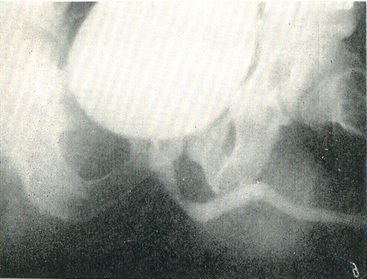

Уретрография. Хворого укладають під кутом 30° до площини стола. На стороні, відхиленої від столу, нога витягнута, на прилеглій до столу - зігнута в тазостегновому і колінному суглобах і дещо відведена назовні. Статевий член натягується паралельно м'яких тканин стегна зігнутої ноги, і 10% розчин сергозина з шприца з конусовидным гумовим наконечником вводять в просвіт сечовипускального каналу (рис. 44). Така уретрография називається висхідною.

У нормі передня частина уретри на ретроградної уретрограмме представляється у вигляді рівномірної смуги діаметром 0,8-1 див. Цибулинна частина уретри утворює розширення у вигляді опуклою донизу дуги. Мембранозна і простатична частини уретри мають вигляд вузької смуги, що відходить від бульбозной уретри під прямим кутом.

Для більш чіткого зображення задньої частини уретри застосовується спадна уретрография: сечовий міхур через тонкий катетер наповнюється контрастним речовиною; після видалення катетера в момент сечовипускання», тобто випускання контрастної рідини при положенні хворого в описаній вище позиції, робиться знімок. Просвіт простатичної уретри на низхідній уретрограмме ясно контурируется (рис. 45, а і б).

Рис. 45. Уретрограммы. а - висхідна уретрограмма; б - спадна уретрограмма

Рис. 44. Положення хворого при уретрографии.